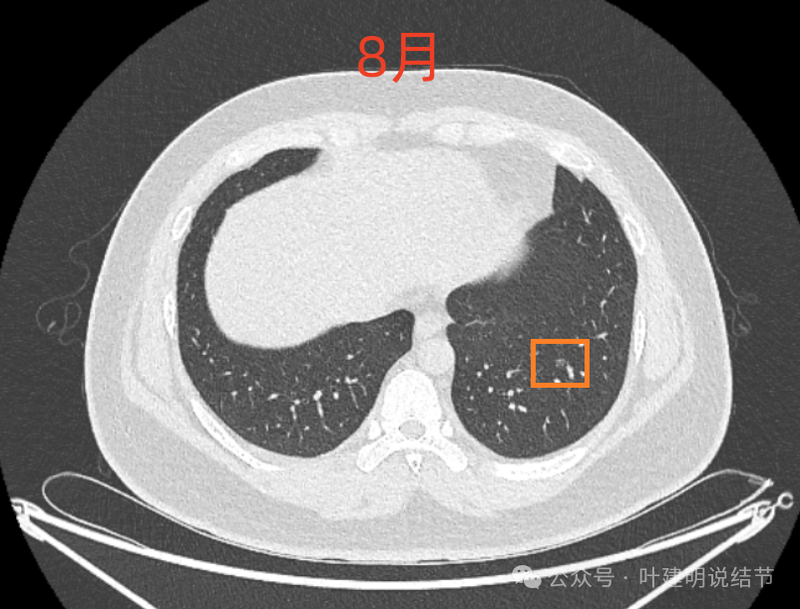

病灶4:

左下磨玻璃微小结节,轮廓与边界清楚,像是肿瘤范畴的,肺泡上皮增生或不典型增生可能性大,近期风险小。

8月时与后来的相仿。

这样的对比,似乎略有变化,又似乎说不上明显变化。本身扫描条件也可能不同。所以我常强调,不要在意过于细微的变化,因为这不影响临床决策。而影响到决策的变化一眼就看出来了。有些同道呀,喜欢拿放大镜看,然后告诉患者有进展,很危险,得尽快手术!只能呵呵了。下面是不同指南与共识对于随访的建议,大家可以自己看。

现在的人工智能辅助诊断系统太过敏感,非常微小的结节都给你找出来,但是对于临床来说并没有多大意义。当结节才几个毫米的时候,既没有办法明确到底是什么,也没有必要明确到底是什么,按照中华医学会肺癌诊疗指南,8毫米以下纯磨玻璃结节或5毫米以下实性结节(包括混合密度结节实性成分不足5毫米)也就是年度复查就可以。所以其实并不一定要在意到底有多少处结节,或者要考虑是什么。主要就关注最主要的病灶,如果主病灶仍没有风险可以年度体检复查,那就可以随访,不能也不必有过大的思想顾虑。我看了你的CT,目前这些结节均风险小,其中右侧桔色框起来的是所谓主病灶,仍是纯磨密度,又还小,考虑不典型增生可能性较大;左下桔色的也是磨玻璃密度,但轮廓不如右上这处清楚,若确实肿瘤范畴,也是原位癌或不典型增生可能性大,但也有少许慢性炎伴肺泡上皮增生或纤维增生的可能性;中叶绿色的密度过高,更符合良性些;右下黄色的过小,11月份的像磨玻璃密度,边界较清,但对比8月时的,此灶不太明显,当然本身过小,也可能没有扫到最明显层面,不过总归风险小,能观察随访(左下的也8月时更显淡和不明显点)。总体上,这几处病灶都是风险还低,可以继续半年到一年复查随访,真若有明显进展并具有一定的风险再来干预处理不影响预后。本身年纪轻,又是多发结节,目前的病灶又都风险低,可以过于积极赶紧处理。意见供参考!